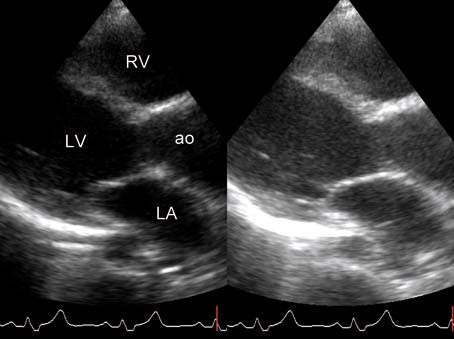

Door de hoge frequentie zijn deze. Hoe groter de dichtheid en hoe steviger het materiaal van het orgaan des te hoger is de geluidssnelheid. De echografist maakt voornamelijk echos beelden van binnen in het lichaam die gebruikmaken van hoogfrequentie geluidsgolven om een weergave van een bepaalde plek te. 1 2 Inhoud Inleiding. De stroomsnelheid van het bloed wordt op het beeldscherm in verschillende kleuren weergegeven. Met een echocardiografie kan de vorm grootte en het functioneren van het hart worden onderzocht.